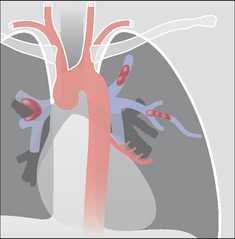

The lung has two distinctive and separate blood supplies (Fig. 30.1):

image Low pressure pulmonary arteries which end in a network of capillaries supplying the alveoli only.

image High pressure bronchial arteries arising from the aorta. Their sites of origin can vary—usually from the proximal descending aorta. Typically, two bronchial arteries supply the left lung and a single bronchial artery supplies the right lung. These arteries feed the bronchial walls up to and including the terminal bronchioles. They also supply the connective tissue of the lung as well as the visceral pleural membrane.

Figure 30.1 The two separate blood supplies to the lungs. The bronchial arteries (high pressure) arise from the aorta. The pulmonary arteries (low pressure) arise from the right side of the heart.